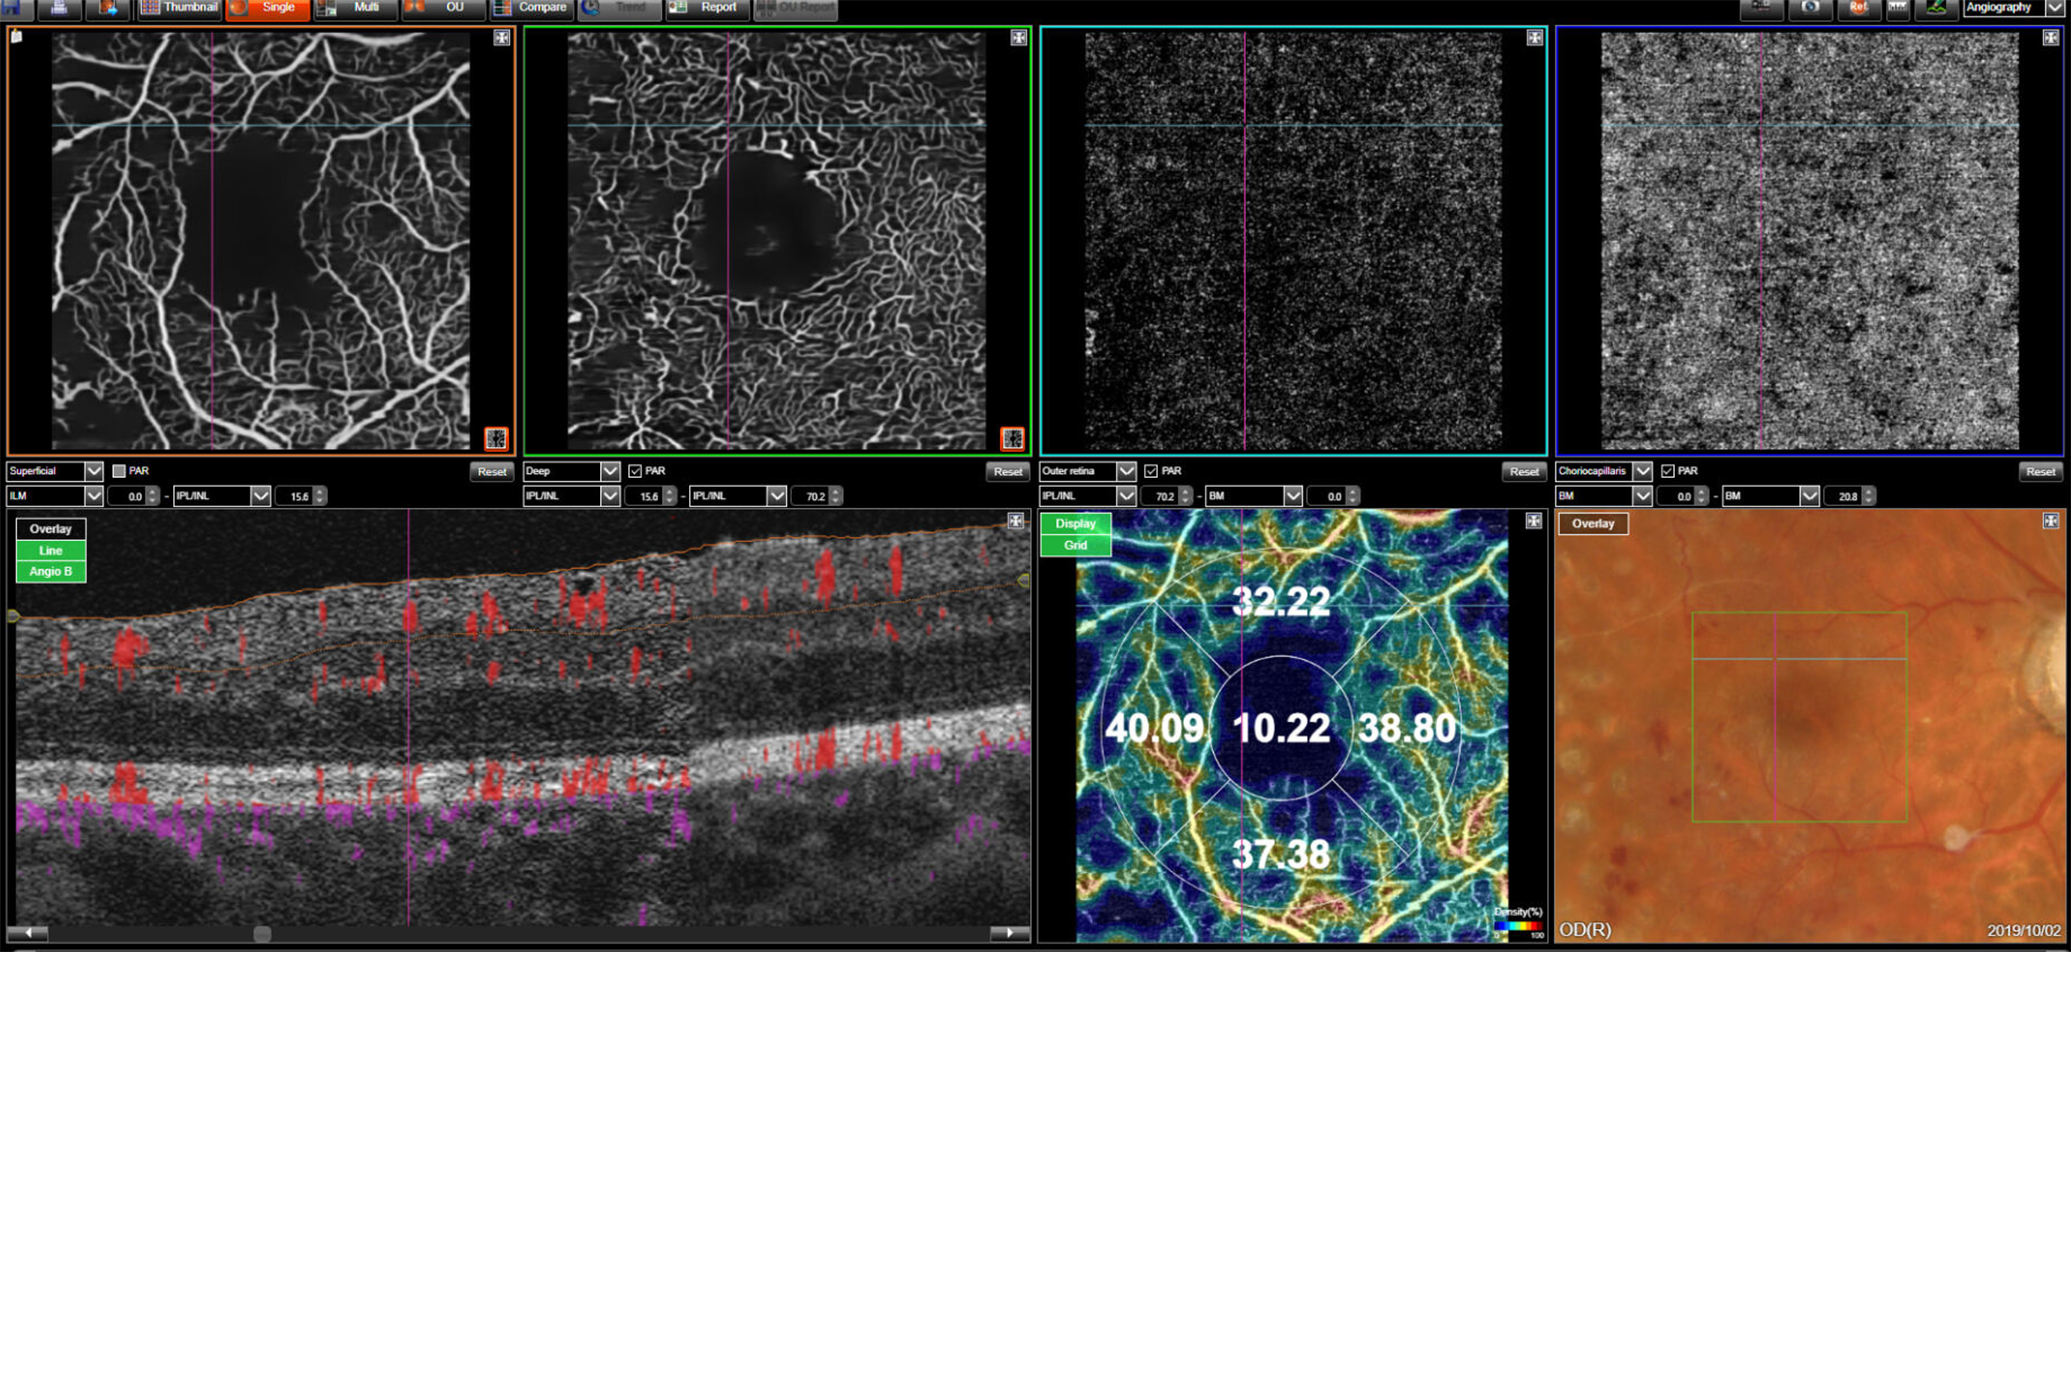

Maestro2

Introducing automated OCT, true color fundus photography, and automated OCT-A in one instrument.

With the touch of a button, OCT-A provides instantaneous vascular structure information – from our world-renowned, multi-modal OCT solution.

Courtesy: Dr. Patrick SPORTIELLO, MD,FEBO, Ophthalmology Practice, Issoire, France

OCT-A data can be quantified with OCT-A density maps and associated metrics.